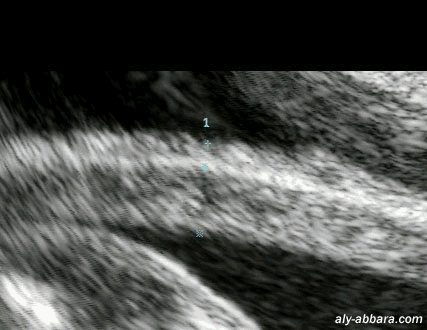

L'aspect échographique du segment inférieur de l'utérus normal à la fin de grossesse